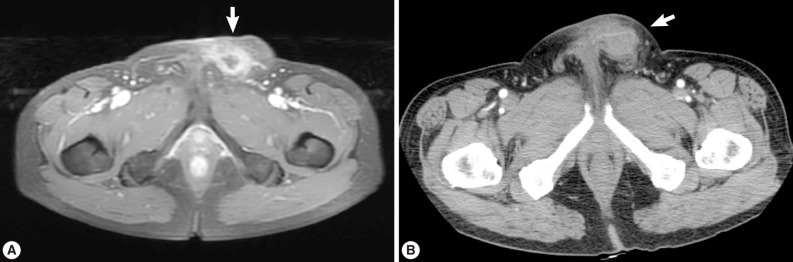

A 56-year old male visited our out-patient clinic for pancytopenia. Bone marrow biopsy and karyotype analysis showed myelodysplastic feature with 14% blast count and normal karyotype, indicating MDS, refractory anemia with excessive blast. He received 4 cycles of decitabine treatment during searching for matched unrelated donor, and partial response was shown. Allogeneic peripheral HSCT with myeloablative conditioning regimen consisting of busulphan and cyclophosphamide was performed from a HLA full-matched unrelated donor. However, at day 5 post-HSCT, 5 cm-sized hard and movable mass in the left scrotum and multiple palpable lymph nodes was detected at the left inguinal area. Pelvic magnetic resonance imaging and computed tomography were done and it was suspected initially as a myeloid sarcoma in the subcutaneous fat layer of the left scrotum and pathologic lymphadenopathy at the left inguinal area (Fig. 1). In order to confirm the diagnosis, gun biopsy was done on the left scrotal mass to avoid bleeding due to thrombocytopenia after HSCT. The result of the gun biopsy was inflamation of fibrovascular soft tissues with extensive interstitial eosinophilic infiltrations without evidence of malignancy. Persistent peripheral eosinophilia was also developed after HSCT. Subsequently, IgG antibody tests for paragonimiasis, cysticercosis, sparganosis, and clonorchiasis were done, and the results were positive for sparganosis and negative for all others. We re-evaluated the patient's past history and found out that he had swam in the river and ate raw fish, cow liver, and pork meat frequently when he was young. For a next step, excision biopsy was done as an approach for therapeutic diagnosis after recovery of thrombocytopenia. The cut surface of the biopsied specimen showed a cyst filled with whitish and myxoid tissues, measuring 2.0×0.6 cm (Fig. 2). The biopsy result was severe acute and chronic inflammation and fibrosis with a sparganum worm (Fig. 3). He was discharged after complete wound healing and stabilization of the post-HSCT condition.

Most sparganosis cases present as lumps in subcutaneous tissues or intermuscular fascia, which are non-tender and sometimes resolve spontaneously. Therefore, the diagnosis is often made incidentally by an imaging study or surgical biopsy in many cases. Because of late diagnosis, the sparganum worm is presumed to have lived many years, and even a 10-year survived sparganum was reported [9]. The final diagnosis is done by the surgical biopsy proving the presence of the worm. However, immunodiagnosis is also recommended to establish a preoperative diagnosis when soft tissue tumors are detected in patients living in endemic areas [3].